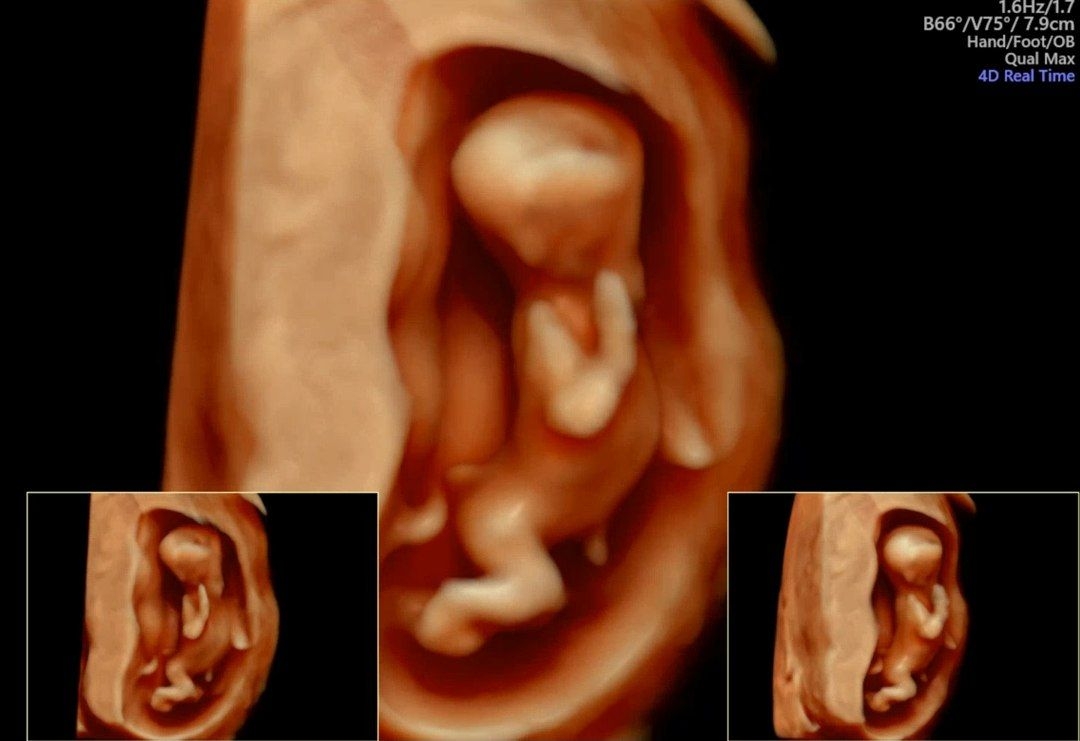

포즈 넘 귀여워용ㅎㅎ 기지개 켜다가 찍힌걸까요?

애기가 길쭉해보여요ㅋㅋㅋ

첨으로 정밀 초음파해서 3D도 봤어요ㅎㅎ 다행히 목 투명대도 정상이고 크기도 잘 크고 있대요. 단면으로 보다가 입체로 보니까 되게 신기하네요ㅎㅎ 팔다리도 엄청 길어보여요>< 다음 진료때 성별알 수 있대서 기다려집니다.